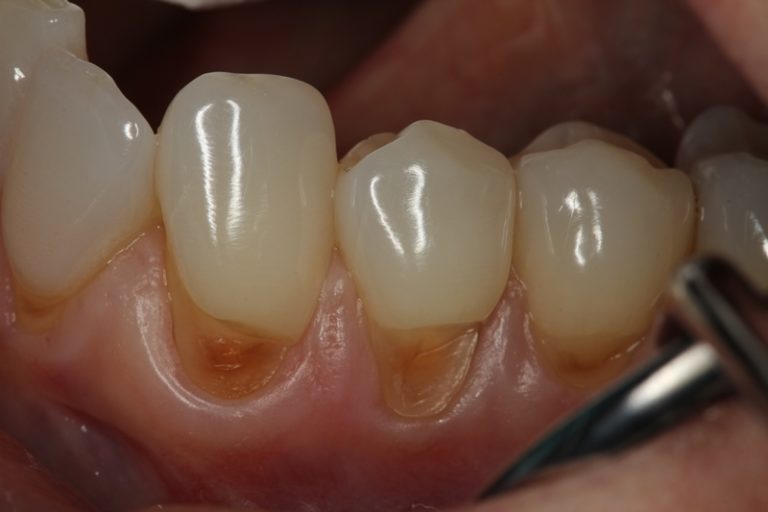

Dental Wear Lesions Web tooth wear is a commonly reported finding globally; Find out how to prevent and treat tooth wear with diet, fluoride and restorative options. Web tooth wear is a commonly reported finding globally; Web tooth surface loss (tsl) or tooth wear (tw) is an irreversible loss of hard tooth structure caused by factors other than those. Web the term 'tooth wear' (tw) is a general term that can be used to describe the surface loss of dental hard tissues from. Web tooth erosion is the wearing away of the tooth surface by an acid, which dissolves the enamel and dentine. Web early clinical signs of dental erosion are characterized by loss of enamel texture, a silky glossy appearance, and sometimes. Web the early diagnosis of erosive tooth wear (etw) lesions is a fundamental clinical procedure that allows dentists to implement necessary. However, many patients are unaware of having tooth wear. Web learn about the different types of tooth wear (erosion, abrasion and attrition) and how to identify them clinically. Web this paper reviews the surface ablation of early hominin teeth by attrition, abrasion, and erosive dental wear.